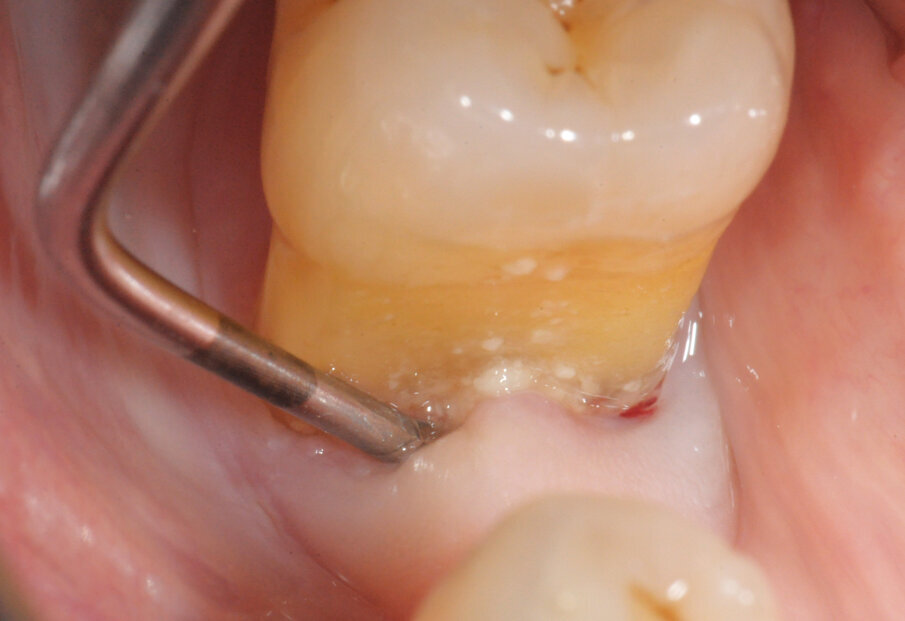

• Perio: utilizzare preferibilmente i Tips sottogengivali (Fig. 2), normalmente indicati in siti parodontali over 5, ma che ci permettono in questo momento di limitare eccessi del getto indirizzandolo interamente in tasca parodontale.